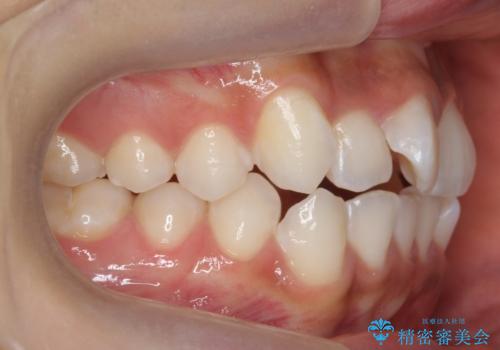

前歯のがたつき 1年かからず治療 マウスピース矯正

- 前歯のがたつきを主訴に来院。

インビザラインで歯を抜かずに並べました。

マウスピースの延長(リファインメント)もなく、短期間で綺麗に並びました。